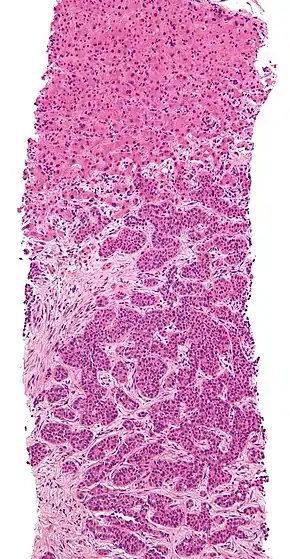

Cross section of a human liver, taken at autopsy examination, showing multiple large pale tumor deposits. The tumor is an adenocarcinoma derived from a primary lesion in the body of the pancreas.

Metastatic disease to the liver